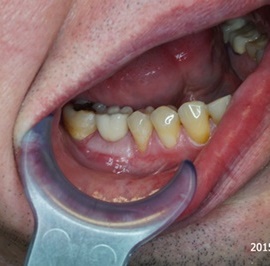

Przedtrzonowce często należą do okolicy estetycznej należy więc zwrócić wzmożona uwagę na poprawną anatomię tkanek kości i dziąsła. Po utracie zęba 25 pacjentka kilka lat chodziła bez jego uzupełnienia, doszło do przesunięcia się zęba 26. U tej pacjentki przed laty był wykonany most jednobrzeżny na czwórce, dość szybko doszło jednak do przeciążenia zęba filarowego, zaniku kości wyrostka i wreszcie pęknięcia korzenia zęba filarowego mostu. Po ekstrakcji i wygojeniu kości stwierdzono ubytek kości wyrostka przekraczający objętość 50% stanu początkowego. Stąd główny nacisk położono na odbudowę tkanek. Uzyskano zadowalający wynik anatomiczny.